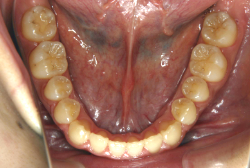

診断の結果、典型的なアングル2級1類の上顎前突です。上下歯列の正中の不一致も見られます。しかし、歯の大きさは平均値に近く、配列の凸凹がそれほど見られません。このまま放置すると、将来的には抜歯を伴う矯正治療を行う可能性が高くなりますが、このタイミングで適切な治療をすると、非抜歯治療が可能かもしれません。

矯正歯科医が着目するのは、奥歯の噛み合わせの位置関係です。前歯の位置にそれなりの差が生じていても、奥歯の位置が正しければそれほど重症という評価にはなりません。このケースの場合は、上下の第一大臼歯の位置関係は、直線的に一致しているタイプでした(矢印が一致)。混合歯列時期の奥歯の位置関係としては、ほぼ正常な状態といえますが、症状から言うと、上の奥歯をもっと後ろに下げてやることができれば、上顎歯列全体に余裕ができるので、凸凹も解消できるし、前歯の傾きを内向きに修正することもできると考えられました。しかしこのまま全体に永久歯が生えきってしまうと、上の前歯が出たままになってしまいますので、生え替わりが完了する前に大急ぎで奥歯を後ろに下げる必要があると判断しました。